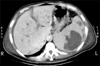

Fig. 2

Computed tomography of the abdomen demonstrating a large splenic abscess with multiple liver abscesses.

A simple X-ray showed collapsed consolidation on the left lower lung field and a air fluid level within a cavitary lesion on the left upper quadrant of the abdomen (Fig. 1). The CT revealed a large splenic abscess, multiple liver abscesses, bronchopneumonia in left lung with left pleural effusion (Fig. 2). Empiric antibiotics therapy with levofloxacin, amikacin sulfate and metronidazole was started, but the fever did not subside. Modification of antibiotics was applied to third generation cephalosporine and metronidazole. On the 8th day of admission, melena was suddenly developed. Emergency endoscopy showed isolated fundal varices in stomach with surface erosion and hematocyst (Fig. 3). Variceal bleeding was successfully controlled by endoscopic variceal band ligation. Aspirate of splenic abscess had chocolate color, foul odor and cultivated anaerobic bacteria, Eubacterium limosum. Abdomen ultrasonography revealed intrahepatic portal vein thrombosis and massive ascites with multifocal hypoechoic hepatosplenic abscesses (Fig. 4). In order to investigate the cause of the portal vein thrombosis, detailed coagulation profiles were evaluated. Anti-cardiolipin antibody IgG was 28.1 GPL (normal <20 GPL) and antineutrophil cytoplasmic antibody was positive. Prothrombin time and activated partial prothrombin time were normal, fibrinogen was 897 mg/dL (normal 170~440 mg/dL), FDP was 20 µg/mL and D-dimer was positive. Antithrombin III, lupus anticoagulant, antigenic protein C and antigenic free protein S were all negative. After bleeding stigma disappeared on second endoscopy, low molecular weight heparin (LMWH) was started for management of acute portal vein thrombosis. Since then, he had been treated with oral antibiotics for 3 months and LMWH daily subcutaneous injection for 6 months. Even after the portal vein thrombosis and abscesses were completely resolved, IgG anti-cardiolipin antibody was still elevated by 26.8 GPL. He has been regularly followed in out-patient clinic with continuous ingestion of oral anticoagulants.